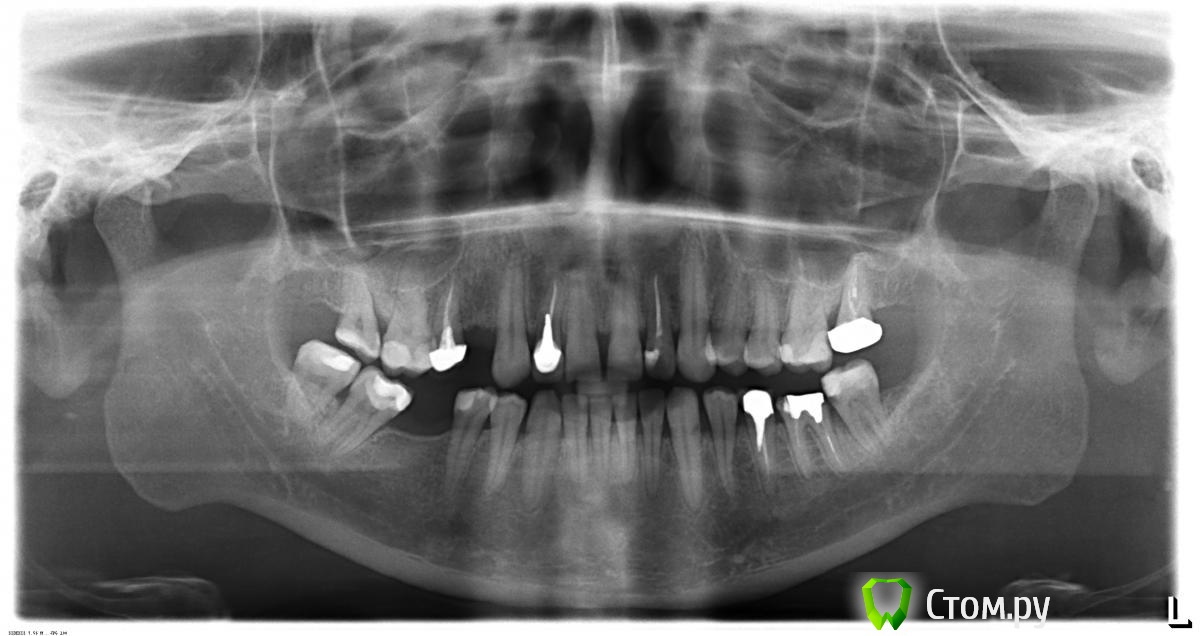

moonlight Опубликовано 5 июня, 2014 Поделиться Опубликовано 5 июня, 2014 (изменено) Добрый день! Зарегистрировалась на форуме, чтобы обсудить наболевшее... Год назад сломала 12 зуб, в нем был уже давно пломбированный канал. Мне поставили металлический штифт, на него металлокерамическую коронку. С первого же дня я почувствовала во рту кислый привкус, который не прошел и по сей день. После чистки зубов он не исчезает. Эпицентр находится в том месте, где коронка соприкасается с десной. Где-то полгода назад мне замеряли токи, полагая, что это гальваноз - токов не обнаружилось. За отсутствие гальваноза говорят еще и хорошие спокойные внешне десны. У меня аллергическая реакция на какие-то неблагородные металлы, по крайней мере, бижутерию и часы носить я не могу, уже через несколько часов начинается сильный зуд и мокнущие прыщики, так же не могу носить и джинсы - мокнет и чешется под металлической клепкой. Поэтому, почти две недели назад мне сняли металлокерамическую коронку и поставили временно пластмассовую. Изменений не произошло. Терапевт утверждает, что при нажатии на десну возле 12 зуба, она видит капельку экссудата ( не гнойного). К концу месяца планируется выемка штифта, хотя врач и говорит, что дело это очень рискованное. К слову сказать, панорамный снимок показал, что штифт несколько смещен по оси, но точно определить, перфорирован ли канал, не удалось даже по 3D снимкам. Еще врач порекомендовал мне провести обследование на аллергические реакции на металлы - но, похоже, в НиНо таких ал.-панелей нет - обзвонила порядка 15 клиник. Еще несколько слов о моей чувствительности - две недели назад, после установки пластмассовой коронки, на следующий день начался стоматит: укольчиков мне врач делал несколько - вся десна в этом месте покрылась язвочками. Через три дня лечилась у терапевта, стоматит она заклеивала какой-то пленкой, нужно было отбелить зуб, врач поставил мне под временную пломбу отбеливающий препарат, вечером, после того как отошел наркоз, десна сильно раздулась и болела жутко, так, что пульс в ней токал. К утру, правда, все прошло. Через неделю, т.е. вчера, препарат удалили, зуб укрепили стекловолокном и запломбировали. Теперь у меня подозрение, что я имею второй "кислый" зуб, и это не смотря на то, что металла в нем нет. Правда, врач сказал, что возможно это пока от действия препаратов. Хотелось бы услышать версии, что это за болячка такая... Изменено 5 июня, 2014 пользователем moonlight Ссылка на комментарий

n-moonlight Опубликовано 5 июня, 2014 Поделиться Опубликовано 5 июня, 2014 Столько написали, а хотя бы мааааленького снимочка не показали )))Покажите все снимки какие есть, и/или сделайте новыевот Ссылка на комментарий